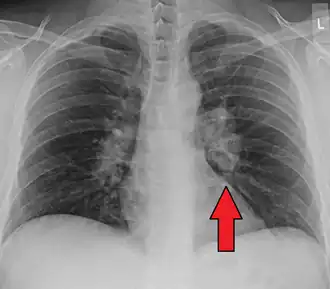

CT scan of the chest showing lymphadenopathy (arrows) in the mediastinum due to sarcoidosis

Diagnosis of sarcoidosis is a matter of exclusion, as there is no specific test for the condition other than the Kveim-Siltzbach test. To exclude sarcoidosis in a case presenting with pulmonary symptoms might involve a chest radiograph, CT scan of chest, PET scan, CT-guided biopsy, mediastinoscopy, open lung biopsy, bronchoscopy with biopsy, endobronchial ultrasound, and endoscopic ultrasound with fine-needle aspiration of mediastinal lymph nodes (EBUS FNA). Tissue from biopsy of lymph nodes is subjected to both flow cytometry to rule out cancer and special stains (acid fast bacilli stain and Gömöri methenamine silver stain) to rule out microorganisms and fungi.[99][100][12][101]